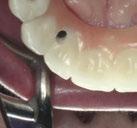

La exploración intraoral (figuras 4 a 8) revela una Clase II molar y canina completa, líneas 1/2 dentarias superior 0,5 mm e inferior 1 mm ambas desviadas hacia la derecha, los incisivos superiores excesivamente protruidos y vestibulizados (seguramente debido a la interposición del labio inferior), resalte de 13 mm y sobremordida 2/3 de corona. La discrepancia oseodentaria

inferior es de -3,5 mm y la curva de Spee de 4 mm.

En la ortopantomografía se aprecia una dentición permanente a falta de la erupción de los 2os y 3 os molares, así como una asimetría ósea con rama y cóndilo mandibular izquierdo menos desarrollado (figura 9), causante de la asimetría facial descrita anteriormente.

El estudio cefalométrico (figura 10) revela una Clase II esquelética por hipoplasia mandibular, patrón braquifacial e incisivos superiores muy protruidos (14,9 mm) y

vestibulizados (52º), e inferiores lingualizados (16 º). El perfil es extremadamente convexo.